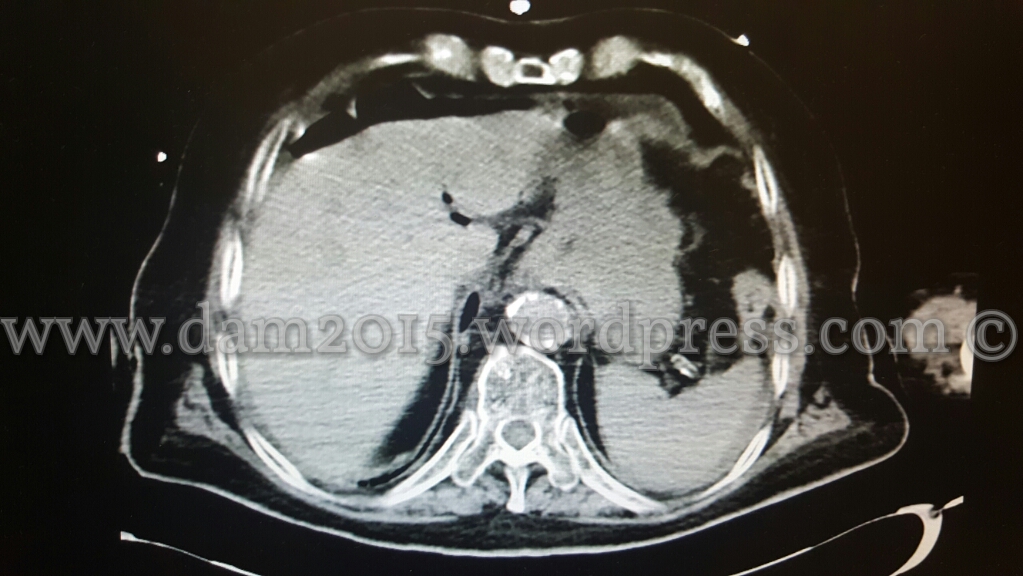

Eseguita TC addome con MDC che mostra aria libera intraperitoneale disposta prevalentemente anteriormente al fegato ed al corpo gastrico, come da perforazione di viscere cavo.

Evidente inoltre marcato ispessimento parietale dell’antro gastrico, della I e II porzione duodenale e del tratto medio-distale dell’esofago (che rimane beante lungo tutto il suo decorso) con edema periviscerale .

Falde di versamento periepatico, tra le anse intestinali, in sede perisplenica e nello scavo pelvico.